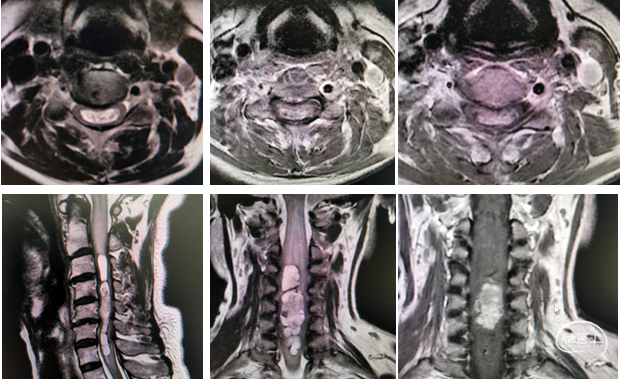

辅助检查:颈椎CT及MR示:脑干下份、C1-7水平脊髓上份见异常信号,累及长度约128mm,部分区域强化明显,内见病灶信号不均匀,增强见实性成分明显强化,相应水平脊髓肿胀等。

图1 颈椎CT及MRI示:脑干下份、C1-7及T1水平脊髓上份见异常信号,考虑室管膜瘤可能性大。

中山大学附属肿瘤医院影像医学中心的刘海彬医师为患者手术提供了高质量的影像学资料,为制定手术方案提供了很大的帮助。完善相关检查,经由神经外科脊髓脊柱亚专业组MDT讨论,骆女士的C1-7、T1髓内肿瘤行C3-6髓内肿瘤显微切除。行肿瘤边界分离,全切肿瘤,避免脊髓损伤,维护脊柱的稳定性,是该手术的目标。张继教授阅片后提出:C3-6髓内肿瘤,脊髓空洞明显,术中需严格肿瘤边界分解,诊断上考虑室管膜瘤可能性大,C3-6后路入路,充分暴露椎板后弓,便可充分显露肿瘤,颈髓后正中沟显露肿瘤,避免术中脊髓牵拉造成对脊髓的挫伤。